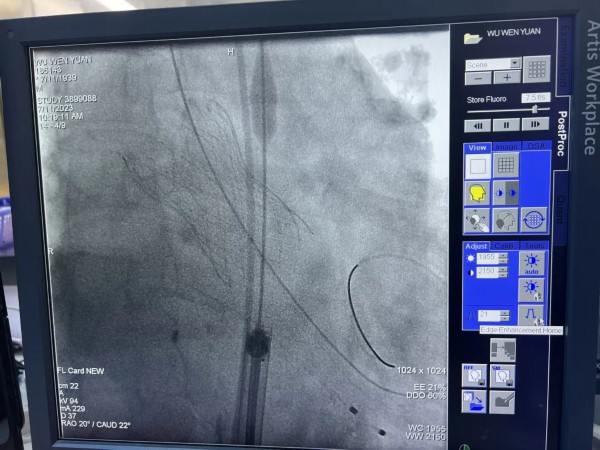

葛均波院士手术中

近日,中国科学院院士、复旦大学附属中山医院心内科主任葛均波教授携团队到宝山区泛血管疾病诊治中心,为一位84岁高龄的复杂高危心脏病患者进行介入治疗。这也是该中心成立1年多来开展的难度最大的一台手术。